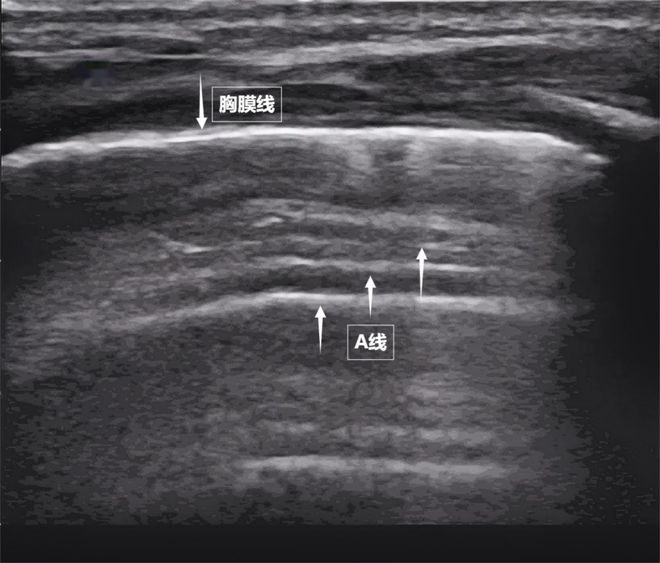

肺是我们体内的一对日夜工作的“风箱”。它们隐藏在胸腔深处,看不见,摸不着,但却与每一次呼吸的质量有关。医生如何“看肺部的状态?检查方法有很多种,但每种都有“缺点”:X光辐射、CT不宜移动、听诊器全靠医生经验……今天,我们就来介绍一种安全便捷的“透视眼”——肺部超声。这种“声探头”以无辐射、实时动态、床边检查等优势,成为观察肺功能的新窗口,不留痕迹却可挑要了解肺部超声波的细微变化,您必须首先了解一个基本原理:超声波通过“回声”产生图像。我们可以将超声波探头视为“声波扩音器”,它发出人耳听不到的高频波,这些声波穿过皮肤和肌肉。d当它们遇到体内的组织器官时,一部分会被吸收,一部分会返回。然后探头接收反弹的声波,计算机最终根据回声的强度、时间和方向在屏幕上构建动态黑白图像。然而,与肝脏和肾脏等实体器官不同,肺部充满了气体。空气是超声波的“天敌”——声波在肺部遇到空气时,大部分会被反射到气体后面,无法深入穿透。就像敲打充气的气球一样。你听到的是清脆的回声,但你在里面感觉不到它。因此,超声波一度被认为是“透过肺部看不见的”。但后来发现,当肺泡充满炎性液体(实变)、肺组织塌陷(肺不张)或胸膜腔内有液体积聚时,病变区域的气体被液体或聚集的组织取代,将原本被肺部气体阻挡的声波展翅起来,排斥病变部位,清晰地显示出病内病变的内部区域。病灶形成的“边界”构成了肺部超声诊断的基础。需要强调的是,肺部超声不能直接观察健康的充气肺组织。相反,它通过检查某些“伪影”(例如胸膜线和 A 线)来检查胸部肺壁交界处的动态变化。此外,它与常规乳房超声检查不同。胸部超声是一个更广泛的概念,涵盖所有胸腔内和胸周结构,如胸壁、肋骨、肺、胸膜和心脏。肺部超声重点检查肺部、胸膜和呼吸肌,是胸部超声的一个针对性很强的重要分支。谁需要肺部超声检查?肺部超声检查虽然好,但并不是每个人都需要定期检查向上。它类似于“侦察”枪,在某些情况下很有用。以下人群特别适合进行肺部超声检查。急诊和危重症患者:对于突然出现呼吸困难、胸痛或外伤的患者,快速医生可以通过肺部超声检查确定其是否患有气胸、胸腔积液或肺水肿。术后或长期卧床患者:有助于发现隐匿性肺炎、肺不张或血栓相关变化。心力衰竭或肾衰竭患者:监测肺水肿的存在和程度。儿童和孕妇:无需辐射,即可反复评估肺部状况。不明原因发热或感染率高者:帮助诊断肺炎、胸膜炎。考试前应该做哪些准备?考试前的准备工作非常简单。考官应穿着宽松的衣服。与医生一起调整坐位或卧位并平静呼吸。氮o 无需快速、无需注射造影剂,且几乎无禁忌症。超声波会使肺部疾病恶化吗?这是广大考生最关心的问题。答案很明确:肺部超声检查不会加重肺部疾病。它类似于“光侦察机”,利用声波传递信息,不留下任何“痕迹”。医学诊断超声波的能量很低,而且不含辐射——它不依赖于有害物质的“释放”,而是依靠人体组织能够探测到的声波的接收来创建图像,就像“用耳朵听回声”一样。目前尚无医学证据表明标准化肺部超声检查会对肺炎、气胸、肺水肿等肺部疾病产生不良影响,也不会损伤肺组织或干扰呼吸功能。相反,可以安全、反复使用:无论是需要dyn的重症患者AMI监测,对辐射敏感的儿童或孕妇,都可以放心接受超声检查。在肺部超声图像中您可以看到的第一个场景是什么:“海岸线和波浪”-胸膜线和一条线。当声音通过胸壁肋骨之间的间隙时,首先遇到靠近肺表面的光滑薄膜——壁层胸膜和脏层胸膜。两者紧密接触,中间没有多余的气体或液体。它们在屏幕上显示为明亮、平滑的水平线,共同形成胸膜线。这条线是肺部的“海岸”。在其下方,由于阿隆的声音通过肺泡中大量气体的强烈反射,一系列均匀间隔、重复的平行于胸膜线的明亮平行线,像海浪一样向屏幕深处出现。这是 A 线(见下图)。 A 线是正常充气的常见标志肺。它的存在直接表明肺表面含有足够的空气,胸膜腔内没有异常的液体或气体。图为正常肺部超声表现第二景:“沙滩与波浪”——肺滑动征。如果我们以实时动态方式调整超声图像,将“图片”变成“电影”,就会出现更加神奇的场景。呼吸时,胸膜线会随着胸廓的运动而轻轻滑动。这就是“肺滑动征”。这意味着肺部和胸壁闭合,呼吸自由顺畅。如果肺壁和胸部之间存在气胸或胸腔积液,这种滑动就会消失。有时,胸膜线下方可能会出现一个小的亮白色闪烁点,称为“彗尾征”(见下图)。当少量、孤立发生时,通常是肺小叶间隔正常的反映,无需担心。这图为正常肺部超声表现的第三个场景:肺部的“呼吸动力泵”——呼吸肌的协调运转。呼吸看似简单,但实际上是多组肌肉共同协作的“集体运动”。肺部超声不仅可以观察肺部的形态,还可以通过实时动态图像“捕捉”呼吸肌的活动状态,为呼吸功能的评估提供独特的视角。膈肌是呼吸肌的“总指挥”,位于胸腔和腹腔之间。平静呼吸时,膈肌收缩下沉,胸腔容积扩大,空气自然吸入;放松时,横膈膜上升,肺部弹性收缩以完成呼吸。在超声波下,可以看到隔膜光滑且呈拱形,随着呼吸的节奏上下移动(见下图)。外部接口骨口肌是“肋间隙的升降器”。当它们收缩时,它们会抬起肋骨并扩张胸腔。前后直径,有助于吸气。这位“黄金搭档”承担着日常呼吸70%的工作量,是维持呼吸的“主力军”。图为隔膜正常超声表现。当身体需要更多氧气时(比如上楼梯),斜角肌和胸锁乳突肌就会“加强”。在极端情况下(例如哮喘发作),腹壁肌肉和肋间内肌很容易被激活。肺部超声这个“侦察兵”,观察肌肉激活的顺序,测量膈肌的厚度和活动度,捕捉矛盾的肌肉运动,动态评估呼吸肌的变化,发现呼吸系统“过度运转”的早期征兆,为医生调整治疗提供准确依据。耳鼻喉科计划。